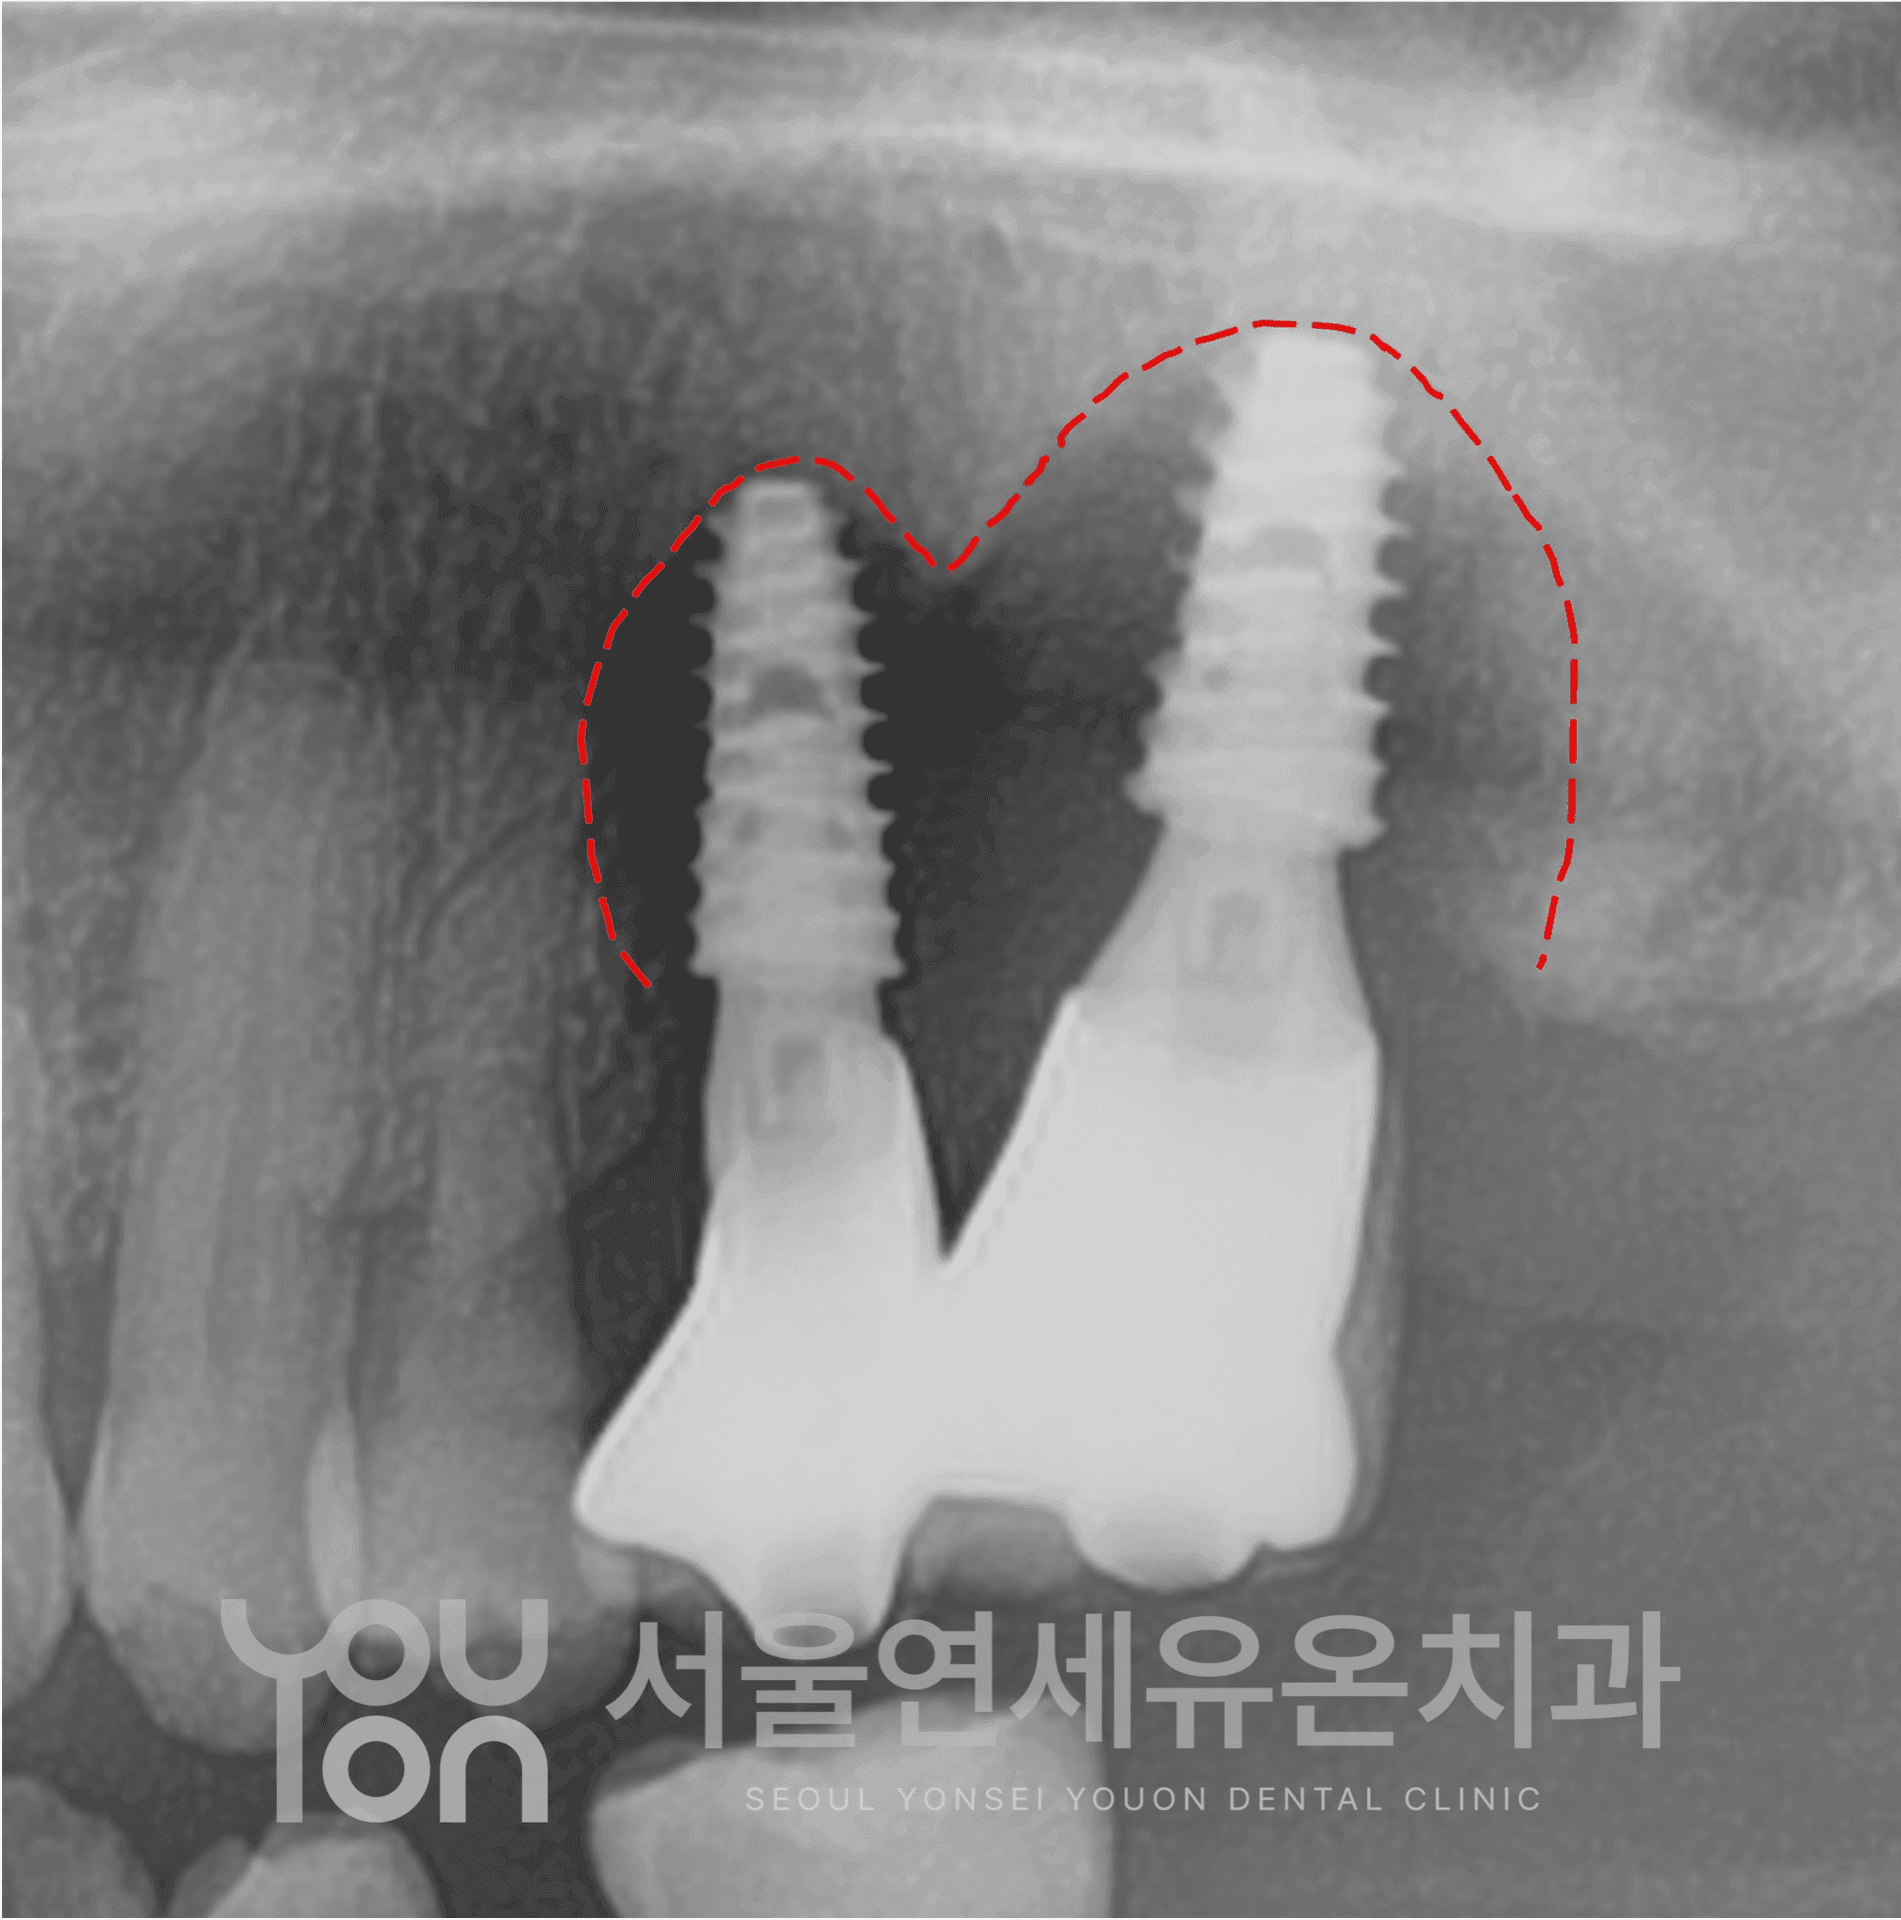

실패 원인을 분석하고,

손상된 뼈와 잇몸 상태를 정밀 진단합니다.

뼈이식, 잇몸이식 등으로 임플란트가

다시 자리 잡을 수 있는 건강한 환경을 마련합니다.